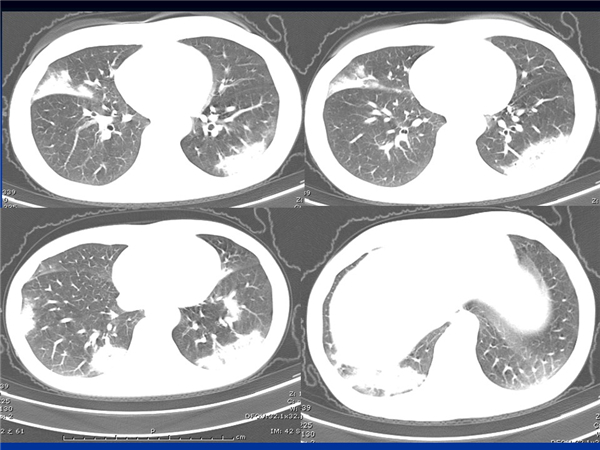

【病例分享】新型冠狀病毒感染肺部CT影像4例(常德市第一人民醫(yī)院)

幻燈片5.jpg